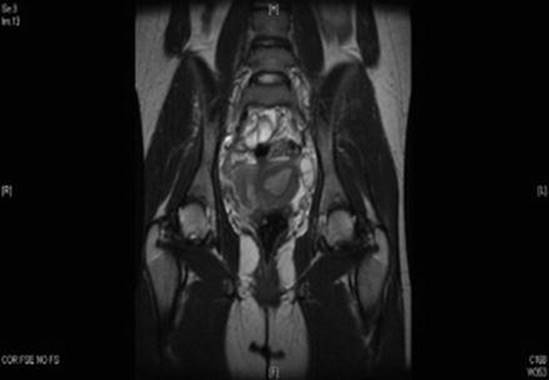

Müllerian Anomalies

MRI is the recommended study to clarify the anatomy in patients with suspected müllerian anomalies (Fig. 4.13) [70]. For the management of pregnancy in a patient with a müllerian anomaly, please see Chap. 3, Pregnancies of Unknown Location and Ectopic pregnancy. For the management of müllerian anomalies resulting in obstructed menstrual flow, please see Chap. 10, Acute Pelvic Pain in Pediatric and Adolescent Patients.

Fig. 4.13

MRI indicating significant myometrial connection between unicornuate uterus and functional, noncommunicating uterine horn (Reprinted from Spitzer et al. [37], with permission from Elsevier and the North American Society for Pediatric and Adolescent Gynecology)